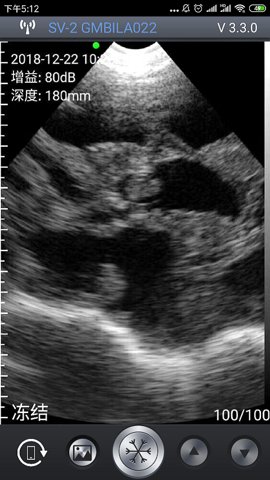

智能B超app是一款专为便携式B超设备而设计的手机应用,通过简单的连接,轻松完成B超检查。这款软件不仅能够满足不同领域的使用需求,还能提升用户的使用体验。无论是在养殖业还是医疗行业,智能B超app都能为用户提供高效的解决方案。现在就来下载这款应用,体验它带来的便利吧!

2、实时图像显示,用户在使用过程中可以直接在智能终端上查看B超图像,方便即时分析和判断。